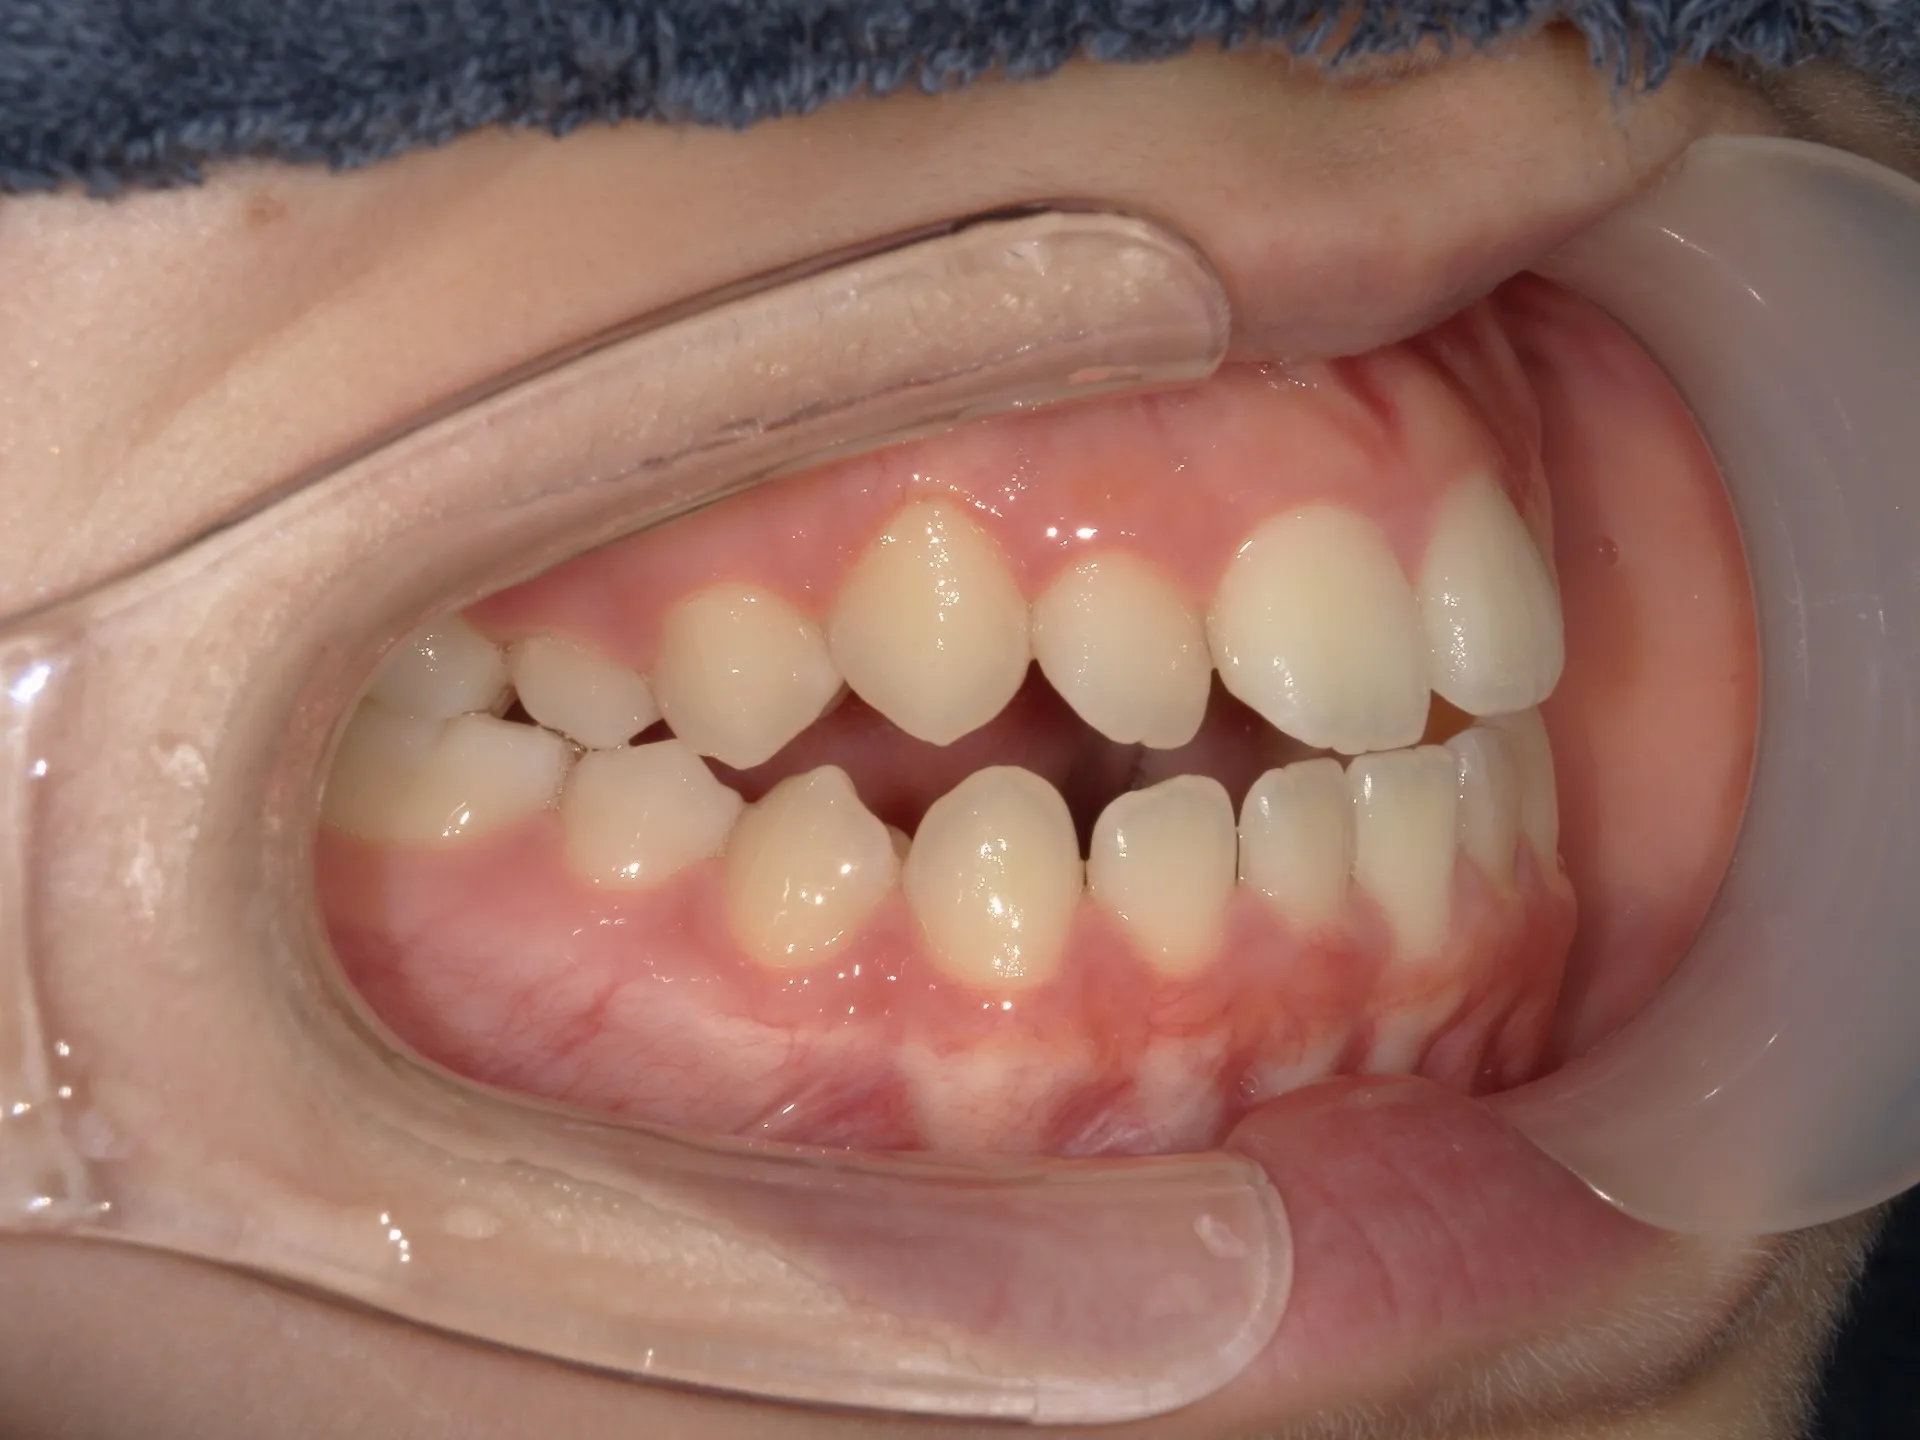

開咬治療前

まず開咬とは、文字通り開いている咬み合わせのことをさします。

分かりにくい方もいるかもしれませんのでもう少し説明すると、今回お見せしている写真では前歯部開咬と呼ばれる開咬です。

臼歯(奥歯)は噛んでいるのに前歯が咬みあわないで開いているという状態のことを前歯部開咬と言います。

さて、治療前の正面観は先ほど述べた通り、前歯部開咬で奥にある舌が見えているのが分かります。